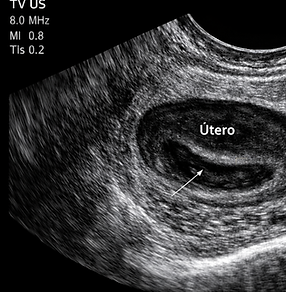

Imágenes Especializadas

En FEMSALUD contamos con una sección especializada dedicada a brindarte información detallada sobre los diversos tipos de imágenes ginecológicas y obstétricas que realizamos. Nuestro compromiso es ofrecerte estudios precisos y confiables, con tecnología de punta y personal altamente capacitado, para acompañarte en cada etapa de tu salud femenina y reproductiva.